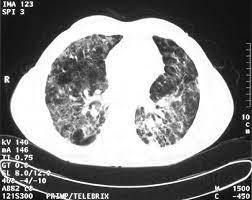

Ct Scan Of The Lungs Axial View Showing Greatly Abnormal Parenchymal Download Scientific Diagram

Postoperative Hypoxaemia Telebrix Aspiration Postgraduate Medical Journal